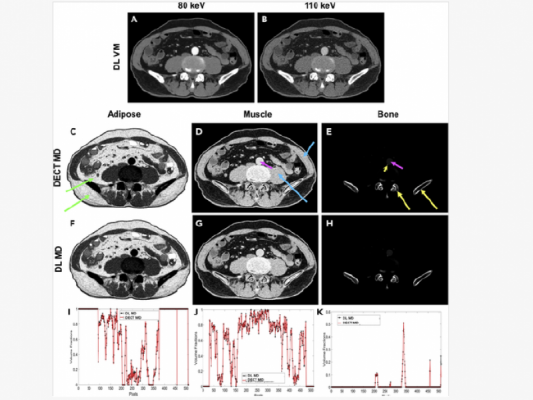

In research published in Patterns, a team of engineers led by Wang demonstrated how a deep learning algorithm can be applied to a conventional computerized tomography (CT) scan in order to produce images that would typically require a higher level of imaging technology known as dual-energy CT.

A higher-level technology called dual-energy CT gathers two datasets in order to produce images that reveal both tissue shape and information about tissue composition. However, this imaging approach often requires a higher dose of radiation and is more expensive due to needed additional hardware.

"With traditional CT, you take a grayscale image, but with dual-energy CT you take an image with two colors," Wang said. "With deep learning, we try to use the standard machine to do the job of dual-energy CT imaging."

In this research, Wang and his team demonstrated how their neural network was able to produce those more complex images using single-spectrum CT data. The researchers used images produced by dual-energy CT to train their model and found that it was able to produce high-quality approximations with a relative error of less than 2%.